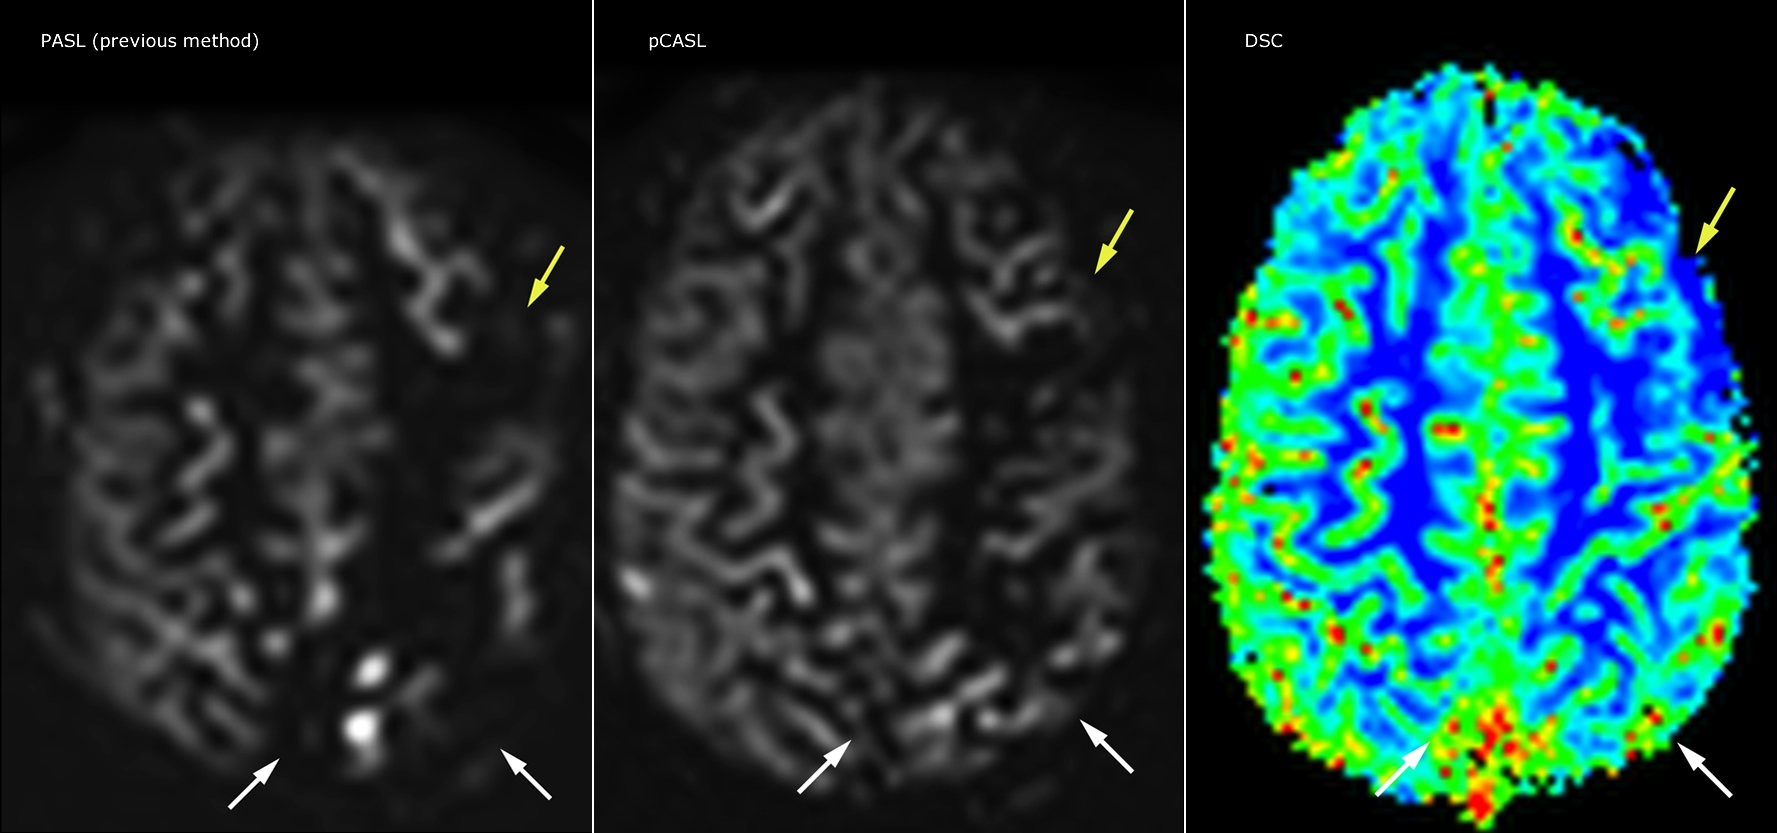

Pseudo-continuous arterial spin labeling (pCASL) was developed for brain perfusion imaging without contrast agent. “This is very desirable in pediatric patients where the general trend is to limit the administration of contrast,” says Dr. Miller.

Dr. Miller uses pCASL for all patients who present with chronic and acute cerebrovascular abnormalities such as acute stroke, as well as patients who present with signs of acute inflammation in the brain, and occasionally in patients with tumors, to assess the perfusion status of their tumor.

“In combination with diffusion weighted imaging, it can help give a more extended assessment of the degree of perfusion abnormality in a patient who is suffering acute ischemia. We have a number of patients who have chronic arterial insufficiency due to prior arterial abnormalities or acquired arterial abnormalities such as sickle cell disease or neurofibromatosis. Sometimes the child’s first manifestation of disease progression is a reduction in brain perfusion before stroke symptoms manifest clinically or in diffusion weighted imaging. We use pCASL to help delineate the perfusion abnormality.”

Growing confidence in specific applications

“We built up confidence in pCASL by comparing it to contrast-based perfusion imaging. Once we had confidence that it was representing what the contrast perfusions were representing, we increased our diagnostic confidence by serial imaging in either the acute stage or the long term stages in a number of patients with arterial abnormalities.

To other new users I would recommend to also start to interpret the pCASL images in comparison with other standard imaging – T2 and FLAIR and DWI – until the user gains confidence in interpreting these images by themselves.”

“A powerful use of pCASL is in patients with chronic cerebrovascular stenosis, where clinicians desire information on how compensatory mechanisms of the brain are performing to enable perfusion to the brain. Often clinicians take into account how the compensatory mechanisms appear to help to provide adequate perfusion to the patient’s brain, and they may intervene surgically or make some other management decision.”

“Another special application is the assessment of cerebrovascular reactivity with a Diamox perfusion exam, where we subtract two sets of pCASL images.”

Efficiencies gained with pCASL

“pCASL has now become more of a first-line scan for assessing perfusion for us, as opposed to DSC-based perfusion imaging with contrast agent. And in patients who were not planned to have contrast, we can perform pCASL for perfusion imaging without need to stop the exam, pull the patient out, and put in an IV. It also negates the postprocessing that’s necessary for dynamic susceptibility contrasts. And it allows us to repeat perfusion imaging in the same patient at the same imaging time, which is helpful in terms of patient motion, or in a situation where a scan needs to be done before pharmacological perfusion imaging.”